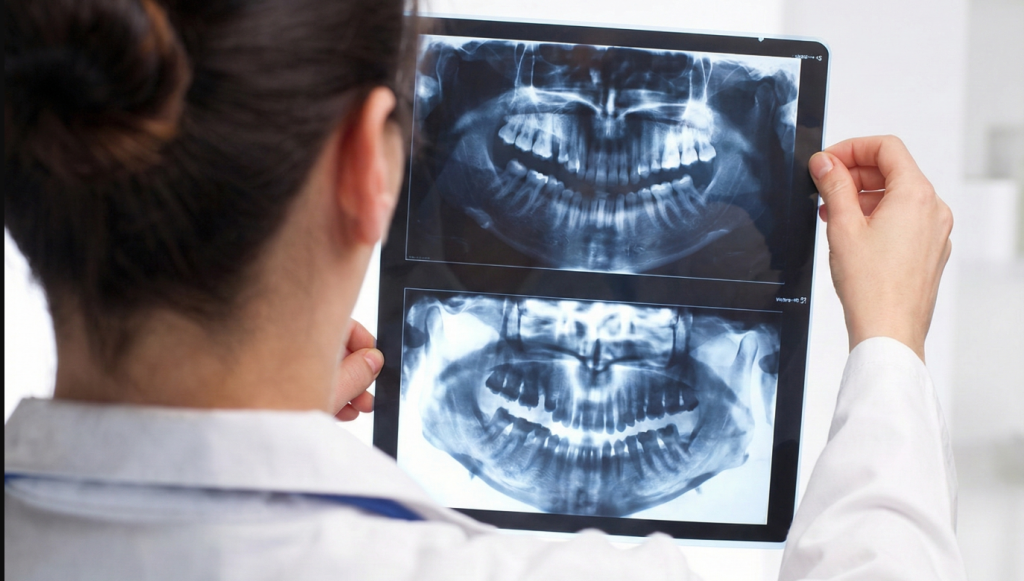

Radiografías extraorales

Estas radiografías se toman desde fuera de la boca y ofrecen una visión más completa de las estructuras dentales y maxilofaciales. Los tipos más comunes son: